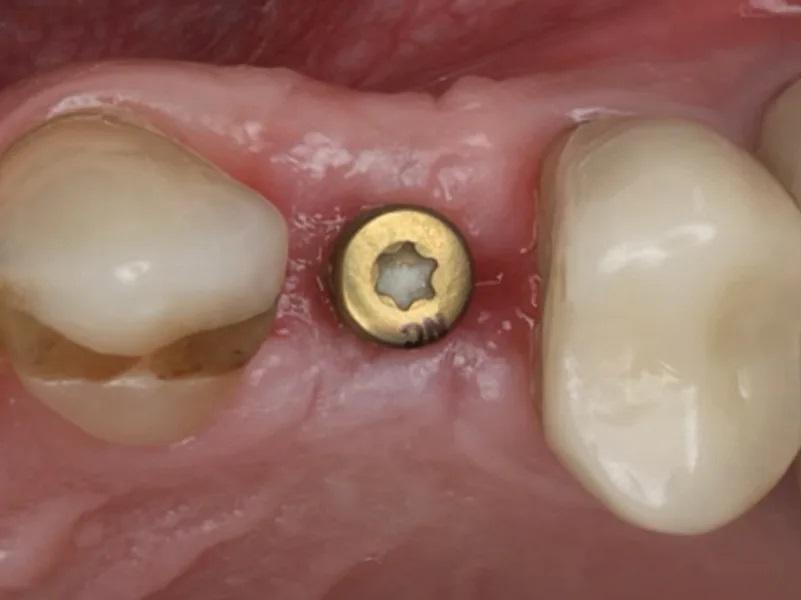

Раскрытие имплантата: Через шесть месяцев после установки имплантата были выполнены оценка мягких тканей и рентгенография (Фото 17). Была проведена местная инфильтрационная анестезия препаратом Septocaine, выполнен гребневой разрез для обнажения ранее установленного имплантата. Была установлена формировательная головка (Фото 18). ПА рентгеновский снимок подтвердил краевое прилегание абатмента к имплантату (Фото 19). Участок был ушит швом ПТФЭ, и пациенту были даны инструкции по гигиене полости рта и послеоперационному уходу. Контрольный осмотр проведен через 2 недели после раскрытия имплантата, мягкие ткани выглядели здоровыми (Фото 20 и Фото 21).

Фото 17. Окклюзионный вид здоровых мягких тканей и ширины гребня через 6 месяцев после установки имплантата.